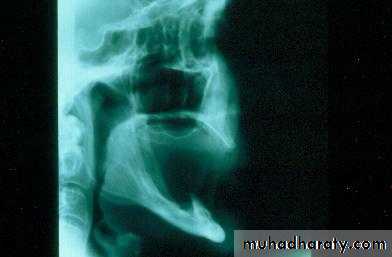

Factors that impact on fit: atrophy

• Atrophy• a. Decreasing bone

b. Increasing soft tissue

1. Atrophya. Decreasing bone

1. Atrophy: accelerated by inflammationa. Infection

b. Poorly fitting dentures … friction

c. Habits … clenching / bruxism